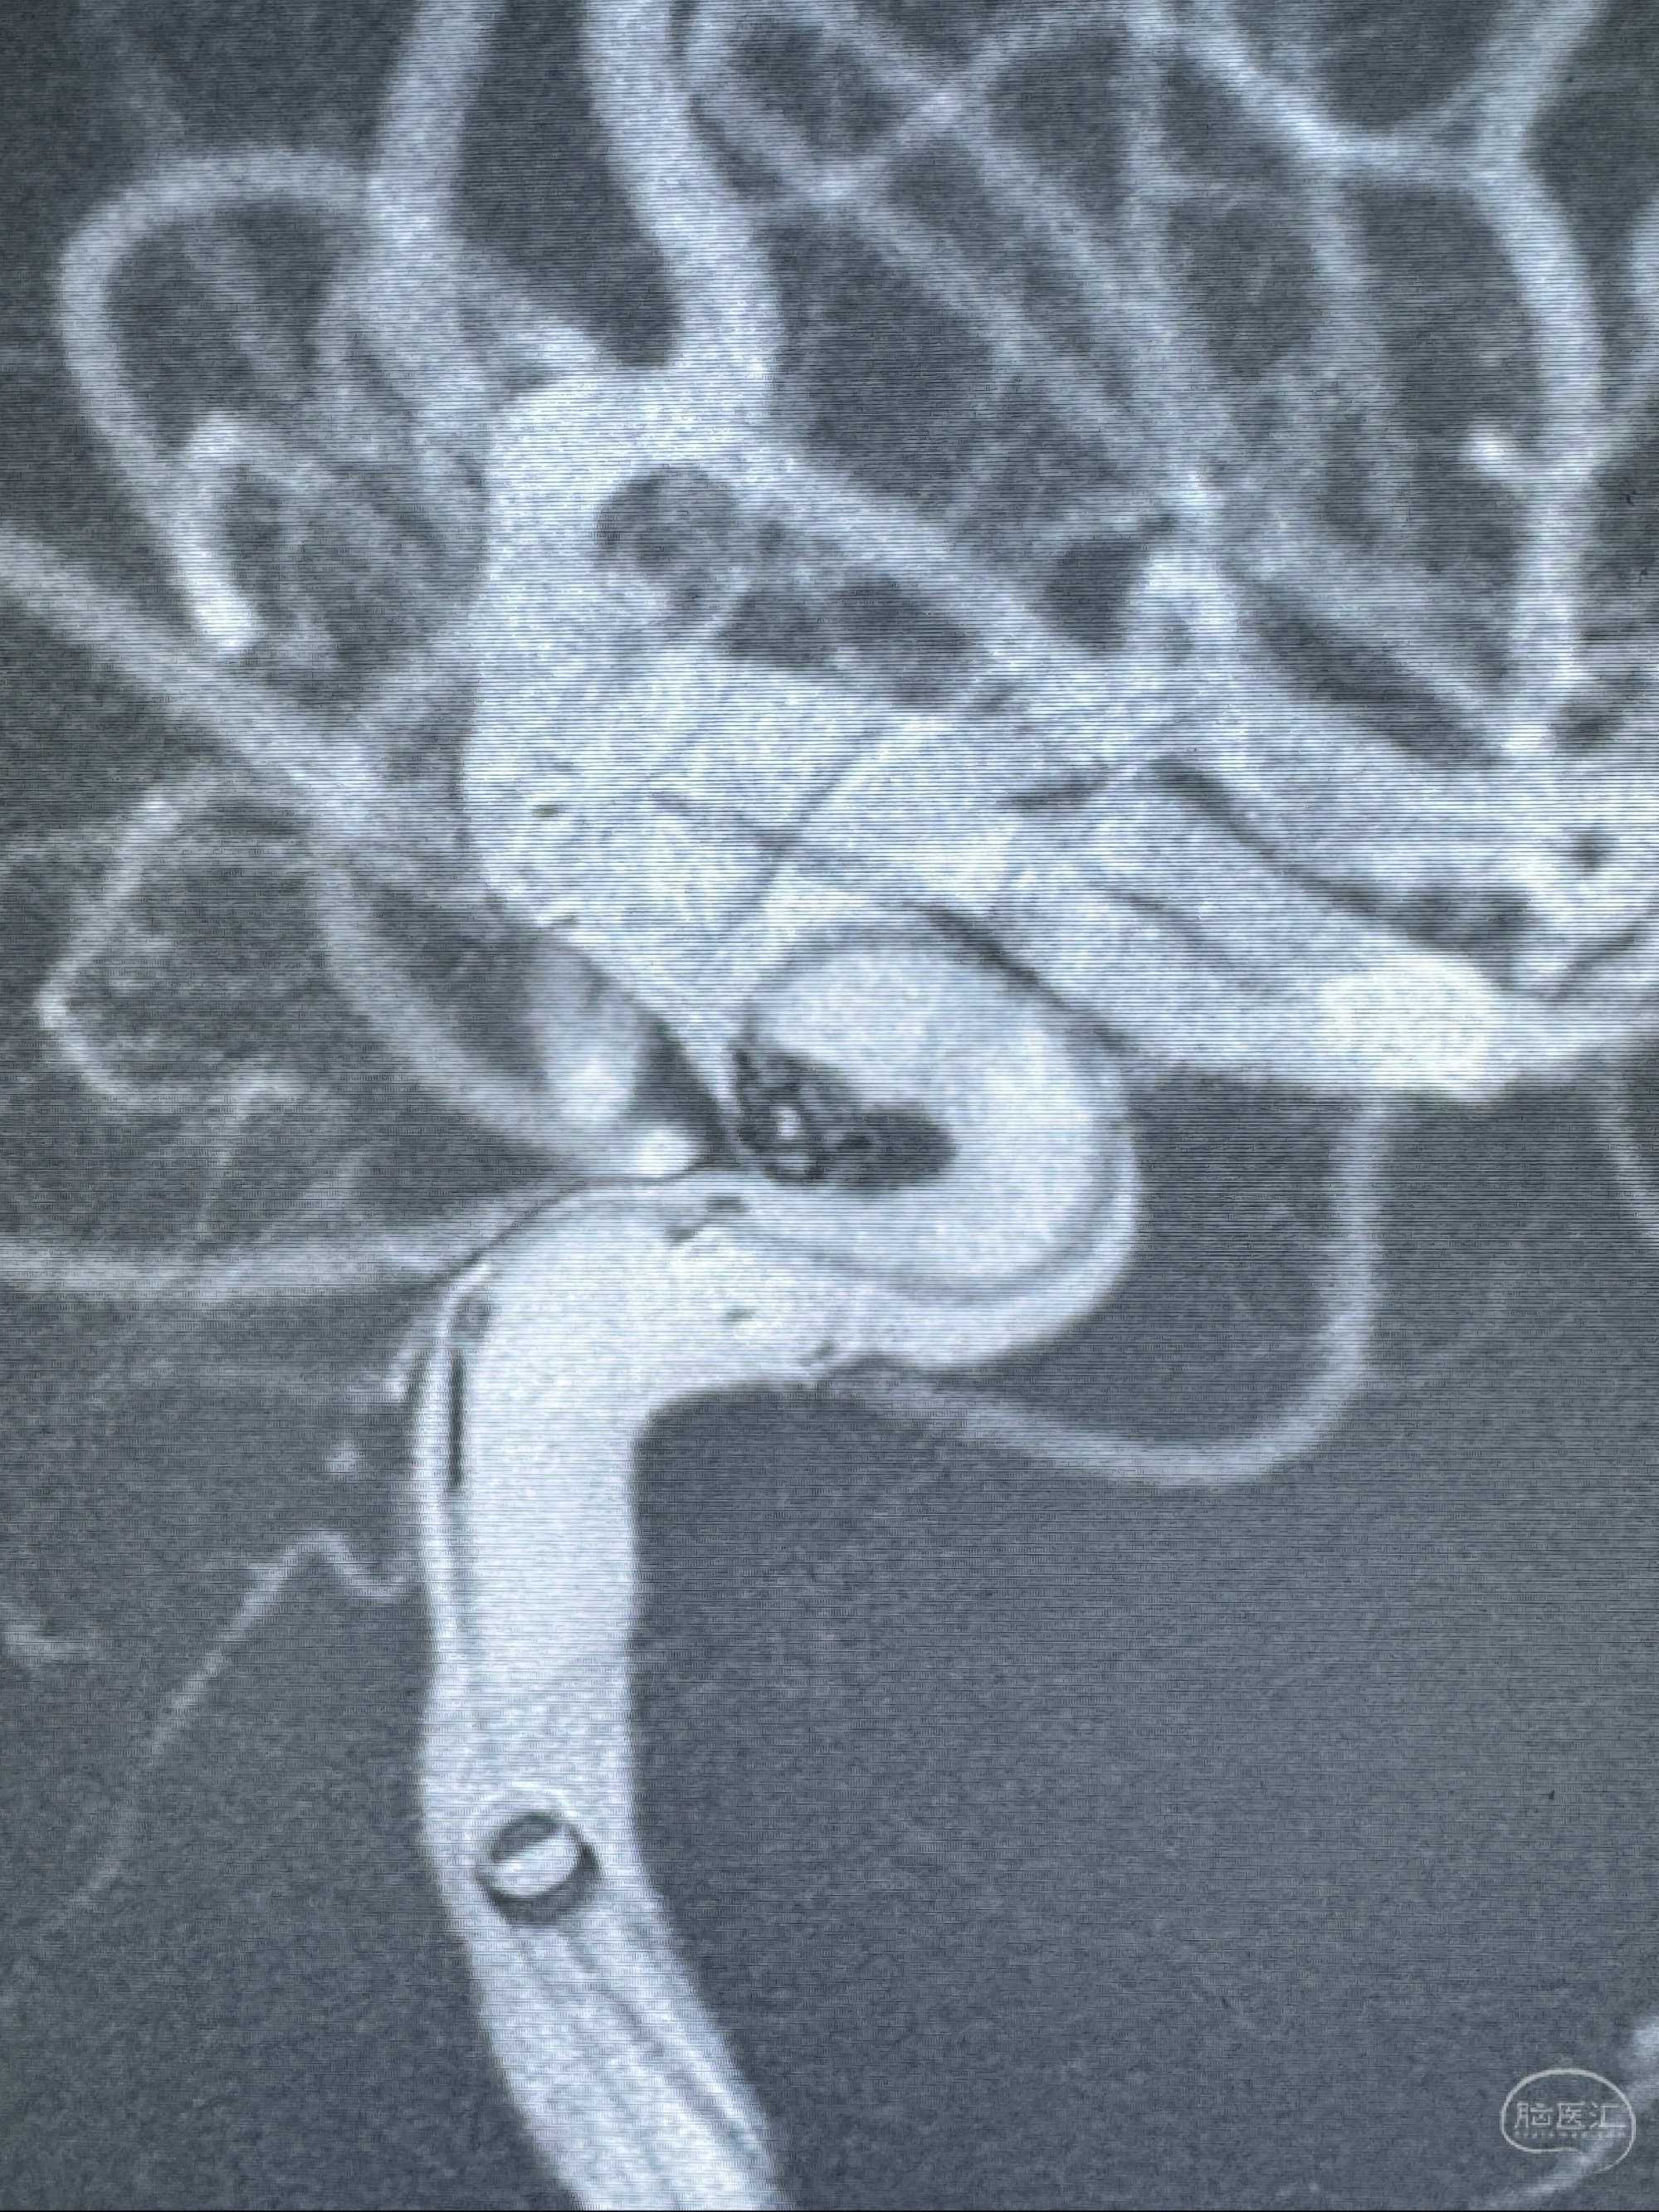

2023-11-13DSA:左侧颈内动脉眼动脉后壁动脉瘤

2023-11-29全麻下行NeuroformEZ4.5-20mm支架辅助栓塞

术后即刻CT